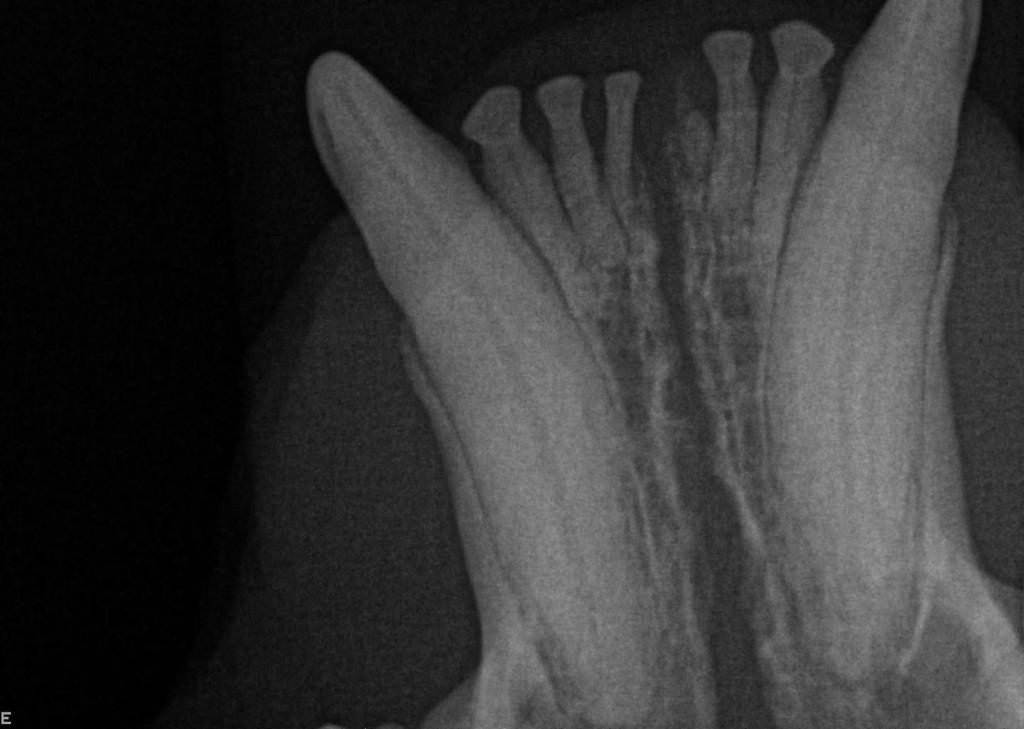

The visible part of the tooth that sits above the gumline is called the crown. However, up to 75% of the tooth structure is below the gumline – the root, periodontal ligament and pulp cavity are all not visible to us without a dental X-Ray.

Dental X-Rays are especially important in feline dentistry. This is because cats very commonly get a disease called tooth resorption, where cells called odontoclasts destroy and dissolve the tooth, later replacing it with bone. This is a painful and irreversible disease and the only treatment is extraction of the affected teeth. Because the disease starts with the tooth root below the gumline and only starts affecting the visible crown of the tooth much later in the disease process, we cannot know which teeth are affected without taking radiographs.

Below shows an image of a normal tooth on dental X-Ray compared to a tooth that is undergoing tooth resorption in the three images below the main one.

Dental X-Rays can also be used in a number of other situations, including to assess for pulp necrosis, periodontal disease, jaw fractures and retained root fragments.